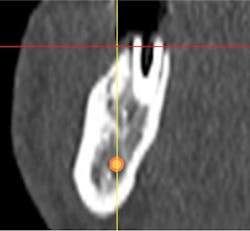

Case study A 58-year-old male with a noncontributory medical history presented to a private practice for a complete rehabilitation of his dentition due to years of bruxism and parafunction. (Fig. 1) After surgical and restorative consultations, a treatment plan was fabricated. The treatment plan included restoring his lost vertical dimension, restoring his natural dentition with porcelain-fused-to-metal full-coverage crowns, and replacing his lost posterior teeth with dental implants. After his vertical dimension was restored with an acrylic bite plate to a position harmonious with TMJ function, crown-lengthening surgery was performed. (Fig. 2)Fig. 2 Six weeks after, the teeth were temporized to develop soft tissue margins/interdental papillae. (Figs. 3 and 3a) The patient was kept in temporaries for three months, during which time an implant was placed in site No. 19. Both the natural dentition and the implant were completed at the same time, three months after implant placement. (Fig. 4) Because of the patient’s occlusal issues, the implant was screw-retained, and the patient was given a maxillary night guard. Three weeks after insertion, the patient presented with a loose abutment screw. The dentist tightened the screw and sent the patient home. This cycle was repeated two more times until the patient presented again with a loose crown, but this time, a fracture implant screw. The dentist attempted to remove the screw with a Cavitron and drilling the implant screw out to release preload, but to no avail. The case was then referred to my office for implant removal.